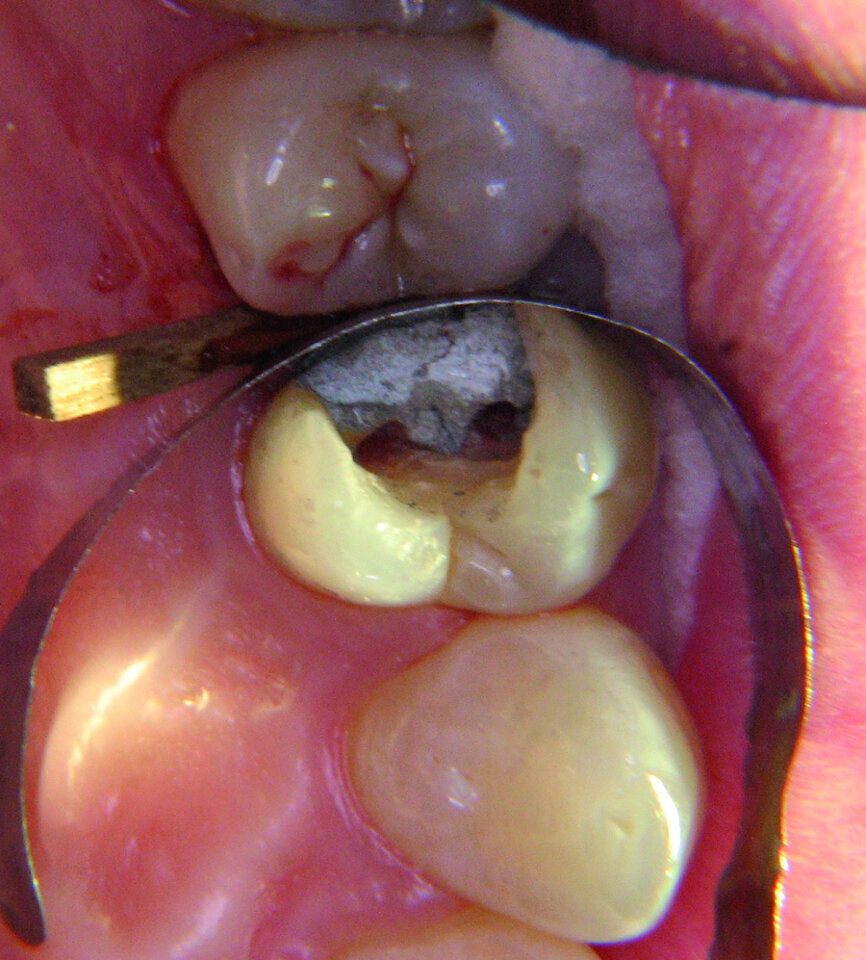

La première molaire supérieure gauche symbolise l’expression de notre sensibilité. Étant donné que cet aspect est souvent réprimé dans notre société moderne, cette dent est aussi très souvent traitée. La première molaire inférieure gauche reflète notre désir d’être aimé. Cette dent est souvent restaurée et est très vite associée à des résultats affligeants. Par exemple, les figures 10a–e montrent une patiente chez qui cette dent s’était fracturée après une rupture sentimentale. Un examen radiographique avait révélé que toutes les autres dents étaient demeurées intactes.